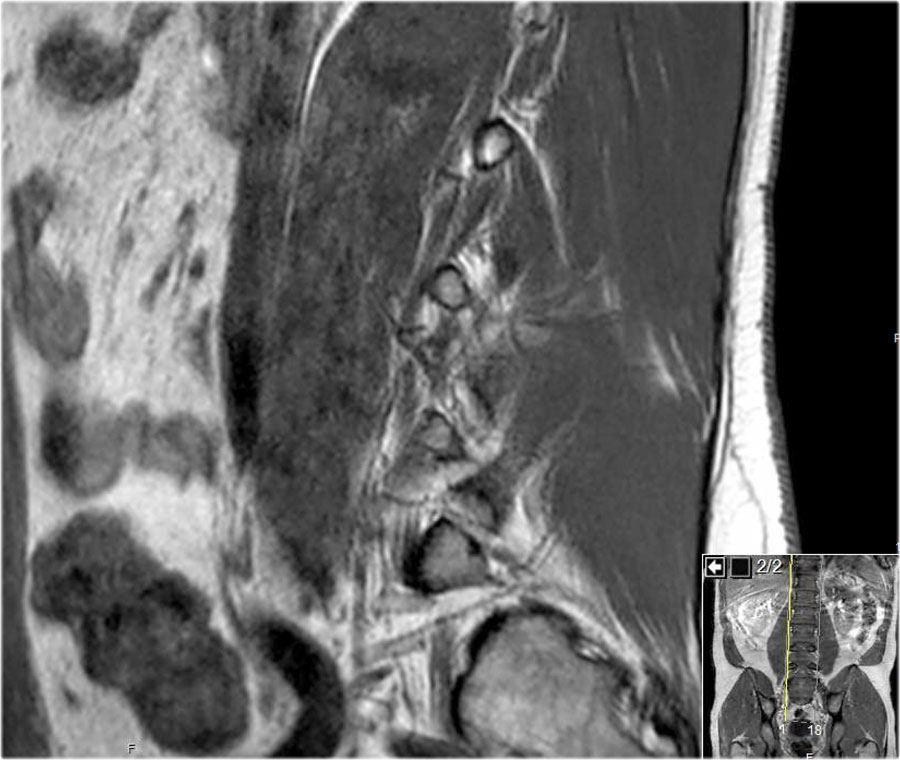

Cuộn qua các hình ảnh để quan sát đường đi của các rễ thần kinh tại mức độ đĩa đệm, ngách bên, lỗ liên hợp và ngoài lỗ liên hợp.

Tại mỗi mức độ có thể thấy các bệnh lý đặc trưng, nhưng có sự chồng lấp đáng kể.

Ví dụ, đĩa đệm có thể thoát vị và gây chèn ép thần kinh tại mức độ đĩa đệm, nhưng cũng có thể di trú xuống tầng thấp hơn và chèn ép rễ thần kinh trong ngách bên, hoặc di chuyển lên trên và gây chèn ép tại mức độ lỗ liên hợp hay ngoài lỗ liên hợp.

Ở bệnh nhân thoái hóa khớp mỏm khớp, các gai xương có thể phát triển vào trong và làm hẹp ngách bên, hoặc phát triển lên trên và làm hẹp lỗ liên hợp.

Khi thoái hóa khớp mỏm khớp nặng xảy ra hai bên, có thể gây hẹp ống sống và chèn ép tất cả các rễ thần kinh tại tầng đó.